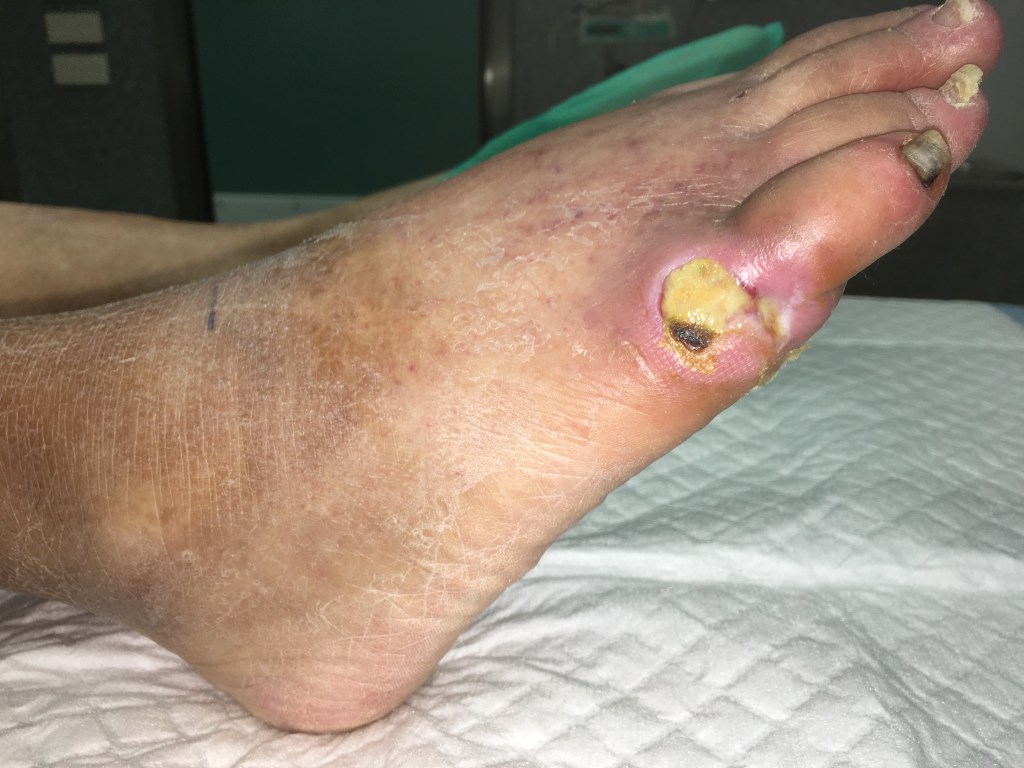

En este caso podemos ver que existe una úlcera profunda, sin tejido de cicatrización.